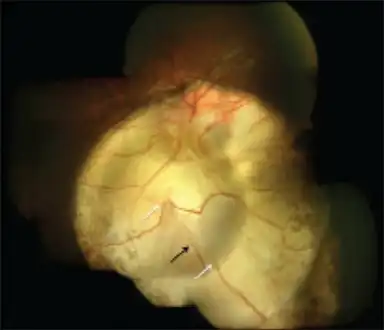

Right fundus with small coloboma at the inferior edge of the nerve that is vertically elongated. Type 5 disc involvement in coloboma of choroid-left eye

Type 5 disc involvement in coloboma of choroid-left eye